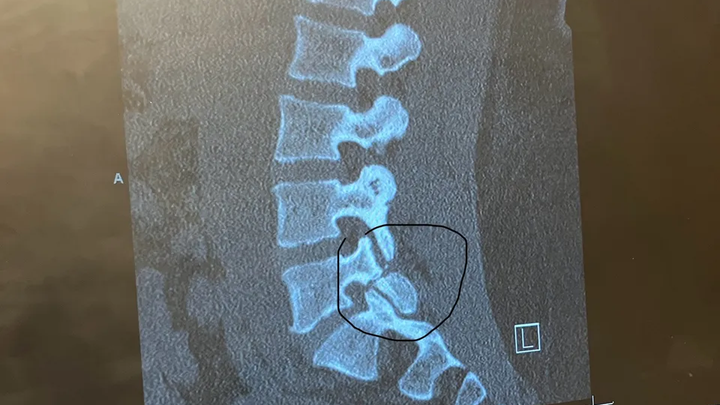

My name is Tradara. I am in my early 30s and have recently been scheduled for an L5-S1 Posterior Lumbar Interbody Fusion. In other words, MAJOR back surgery. I will undergo emergency back surgery—a decision that couldn’t be delayed due to the severity of my condition. While the surgery is necessary to protect my long-term health, the aftermath will leave me in an incredibly difficult place physically and financially.